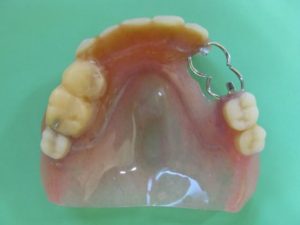

〈義歯治療後〉

治療後は口元に少し張りも出て、お口の形も左右対称になりました。ご本人は知り合いの人に「あなたは歯が良くていいわね!」と言われたと喜んでました。料理がお好きな方で、色々食べられる様になって嬉しいとおっしゃっていました。

上下顎にレジリエンツテレスコープ義歯治療を行いました。